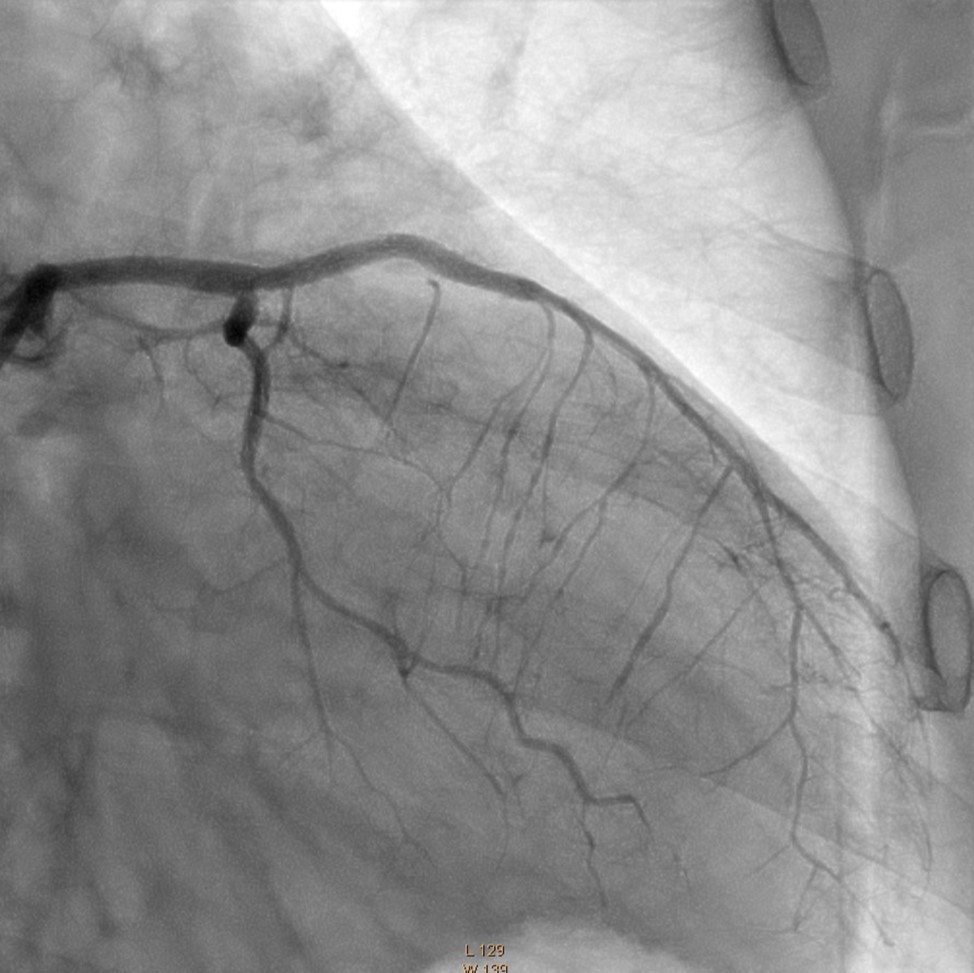

In the first stage, occluded left main and circumflex arteries were recanalized utilizing the support-balloon technique, and CTO wires (Miracle 3™ wire, Abbott Vascular; Runthrough® NS Intermediate wire, Terumo) and balloon pre dilatation was done (Figure 3). In the second stage, the occluded LAD artery was successfully recanalized by utilizing the support-balloon technique, and CTO wires (Figure 3) (due to severe calcinosis the second stage lasted 40 min). In the third stage, LAD artery, CX artery, as well as LMCA and its bifurcation, were stented with 3 drug-eluting stents (Resolute Integrity Zotarolimus DES, Medtronic), the "Culotte Stenting " technique was used for bifurcation stenting (Figure 4), followed by "Kissing Balloon" post-dilatation technique, and finally, proximal optimization technique was performed in the LMCA. The final angiographic image is good, the intervention ended without complications (Figure 5).

Figure 5.Left Coronary Artery, final result of the intervention.